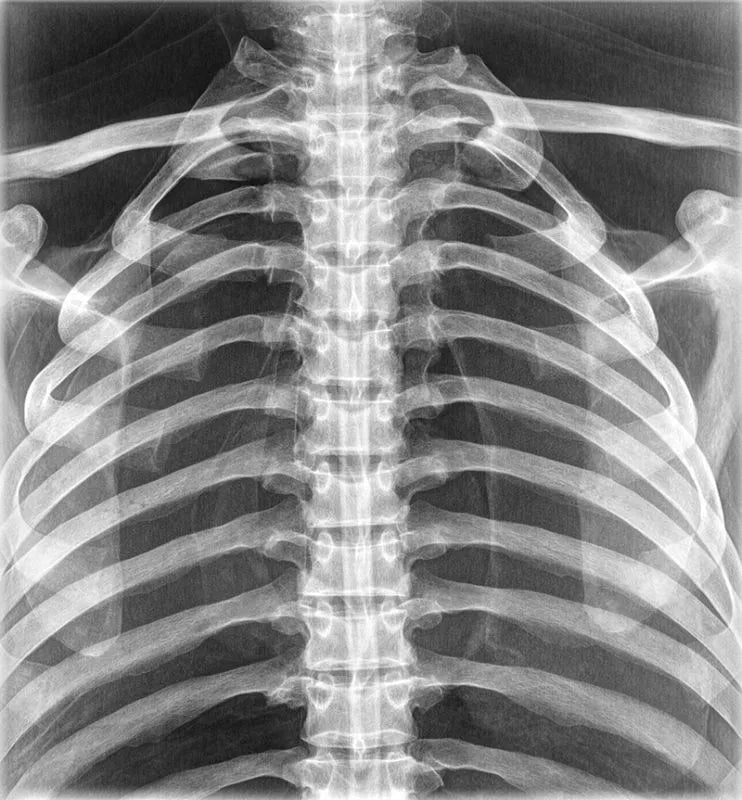

The whole-body X-ray phantom serves for practical training in projection radiography as well as in positioning and positioning techniques. It enables the production of realistic X-ray images under training conditions and depicts anatomical structures in their natural size.

The phantom contains a natural human skeleton. Additionally, the outlines of the larynx, lungs, heart, and kidneys are integrated, appearing as shadows on the X-ray images. This allows for the creation of images that accurately reflect the conditions found in patients. The use of a real skeleton enables the identification of bony landmarks that are not visible in plastic models.

The joints are mounted with full mobility, allowing positioning in common radiological standard positions, including special positions such as the frog position and pronation and supination of the forearm. The arms can be raised, so the phantom can also be used for bone examinations in CT scans. Particular attention was paid during assembly to the realistic representation of the joint spaces.

Each phantom is a handcrafted, unique piece. Variations in size, design, and appearance are possible. Depending on the model, pathological findings may be present. The revised design was developed in collaboration with a German training institution for medical-technical radiology assistants and meets the requirements of modern training concepts.